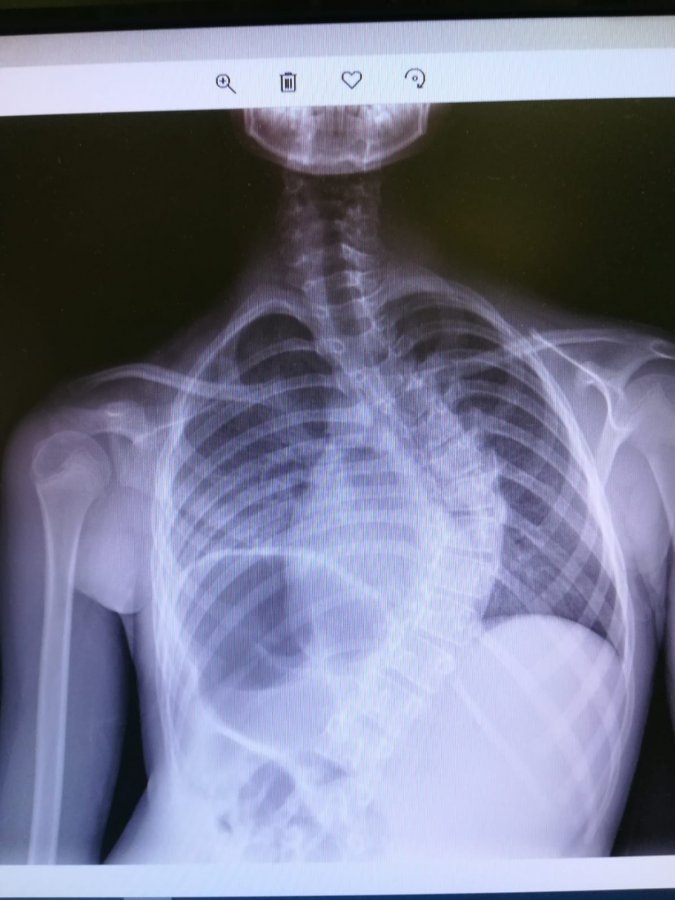

Pierwszą w Polsce operację bez usztywniania kręgosłupa u dziecka ze skoliozą przeprowadzono w Uniwersyteckim Dziecięcym Szpitalu Klinicznym w Białymstoku. Po zabiegu pacjent może wrócić do pełnej aktywności fizycznej.

To zupełna nowość w leczeniu skolioz dziecięcych. Do tej pory prostowało się je przy pomocy specjalnych prętów stabilizujących kręgosłup. Choć poprawiał się komfort życia, to można było zapomnieć o większej aktywności fizycznej pacjenta. Jesienią zeszłego roku w białostockim szpitalu dziecięcym po raz pierwszy skoliozy operowano przy użyciu prętów magnetycznych. U rosnących dzieci wydłuża się je za pomocą specjalnego pilota, bez konieczności kolejnych operacji. Choć to też nowatorska metoda operacji, to jednak kręgosłup nadal pozostawał stale usztywniony.

W końcu marca w Białymstoku wykonano operację korekcji skoliozy idiopatycznej techniką bez usztywniania kręgosłupa, tzw. VBT (ang. Vertebral Body Tethering). To autorskie opracowanie światowej sławy chirurgów kręgosłupa z USA dr Darryl Antonacci i prof. Randal Betz z Institute for Spine and Scoliosis. Metoda ta polega na wszczepieniu w kręgosłup ruchomych prętów elastycznych (wymiennie używa się też określenia śruby elastyczne i taśmy elastyczne), bez usztywniania kręgosłupa. - Pręty umożliwiają dziecku powrót do normalnej aktywności w ciągu sześciu tygodni, nawet z gimnastyką artystyczną i tańcem włącznie - opisywała zabieg prof. Anna Wasilewska, dyrektor szpitala dziecięcego.